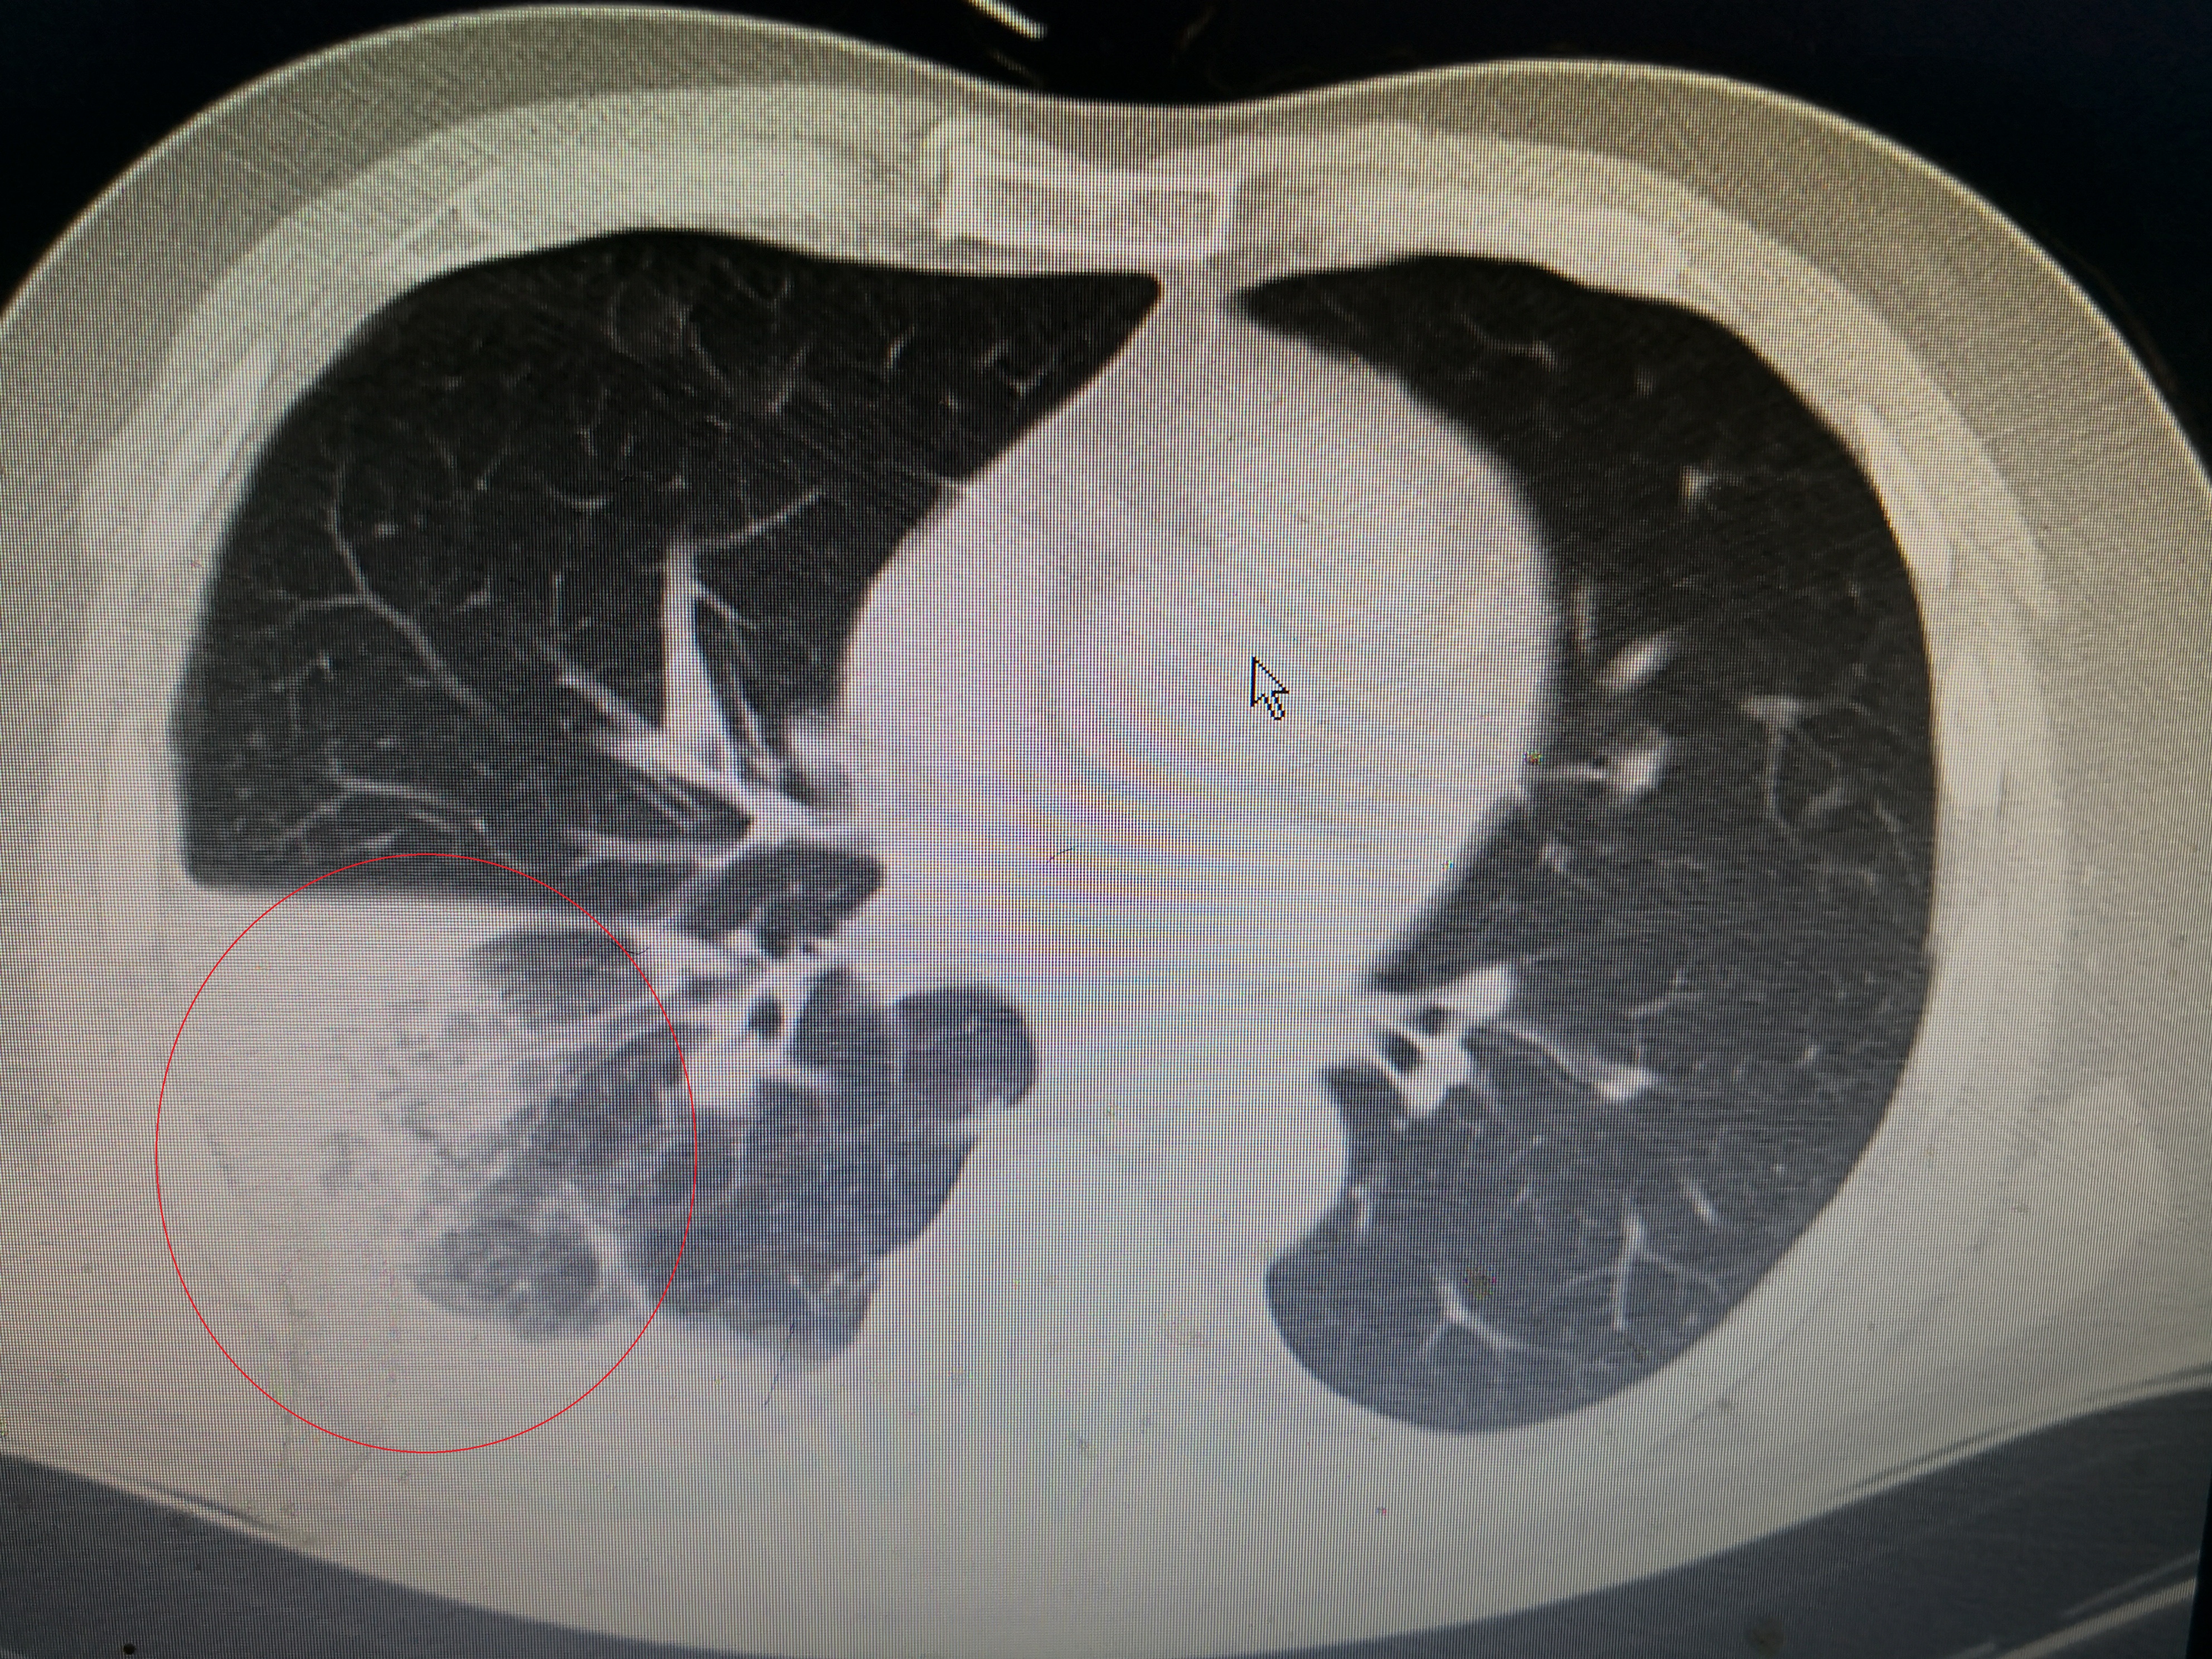

下面这个患者就是近期从西城院区转过来的发热,大片肺炎患者。患者男,55岁,因发热3天到西城院区就诊,体温最高41℃,伴有畏寒、乏力、纳差,咳嗽少痰,伴有顽固性呃逆,没有新冠肺炎流行病学史,但是CT提示右肺大片炎症,在发热门诊隔离抗炎,经两次筛查阴性,但是抗炎效果不佳,仍有高热,转到这边急诊二病区抗炎治疗。

化验白细胞15.48×10^9明显升高,C反应蛋白108mg/l升高,符合经典的社区获得性肺炎标准,所谓社区获得性肺炎(CAP),说白了就是在医疗机构以外得的肺炎,相对来说肺炎链球菌、支原体等多见,耐药性少见。该患者白细胞和C反应蛋白升高符合细菌感染表现,而且血气氧分压65mmHg,明显低氧,接近于I型呼吸衰竭,属于重症肺炎。